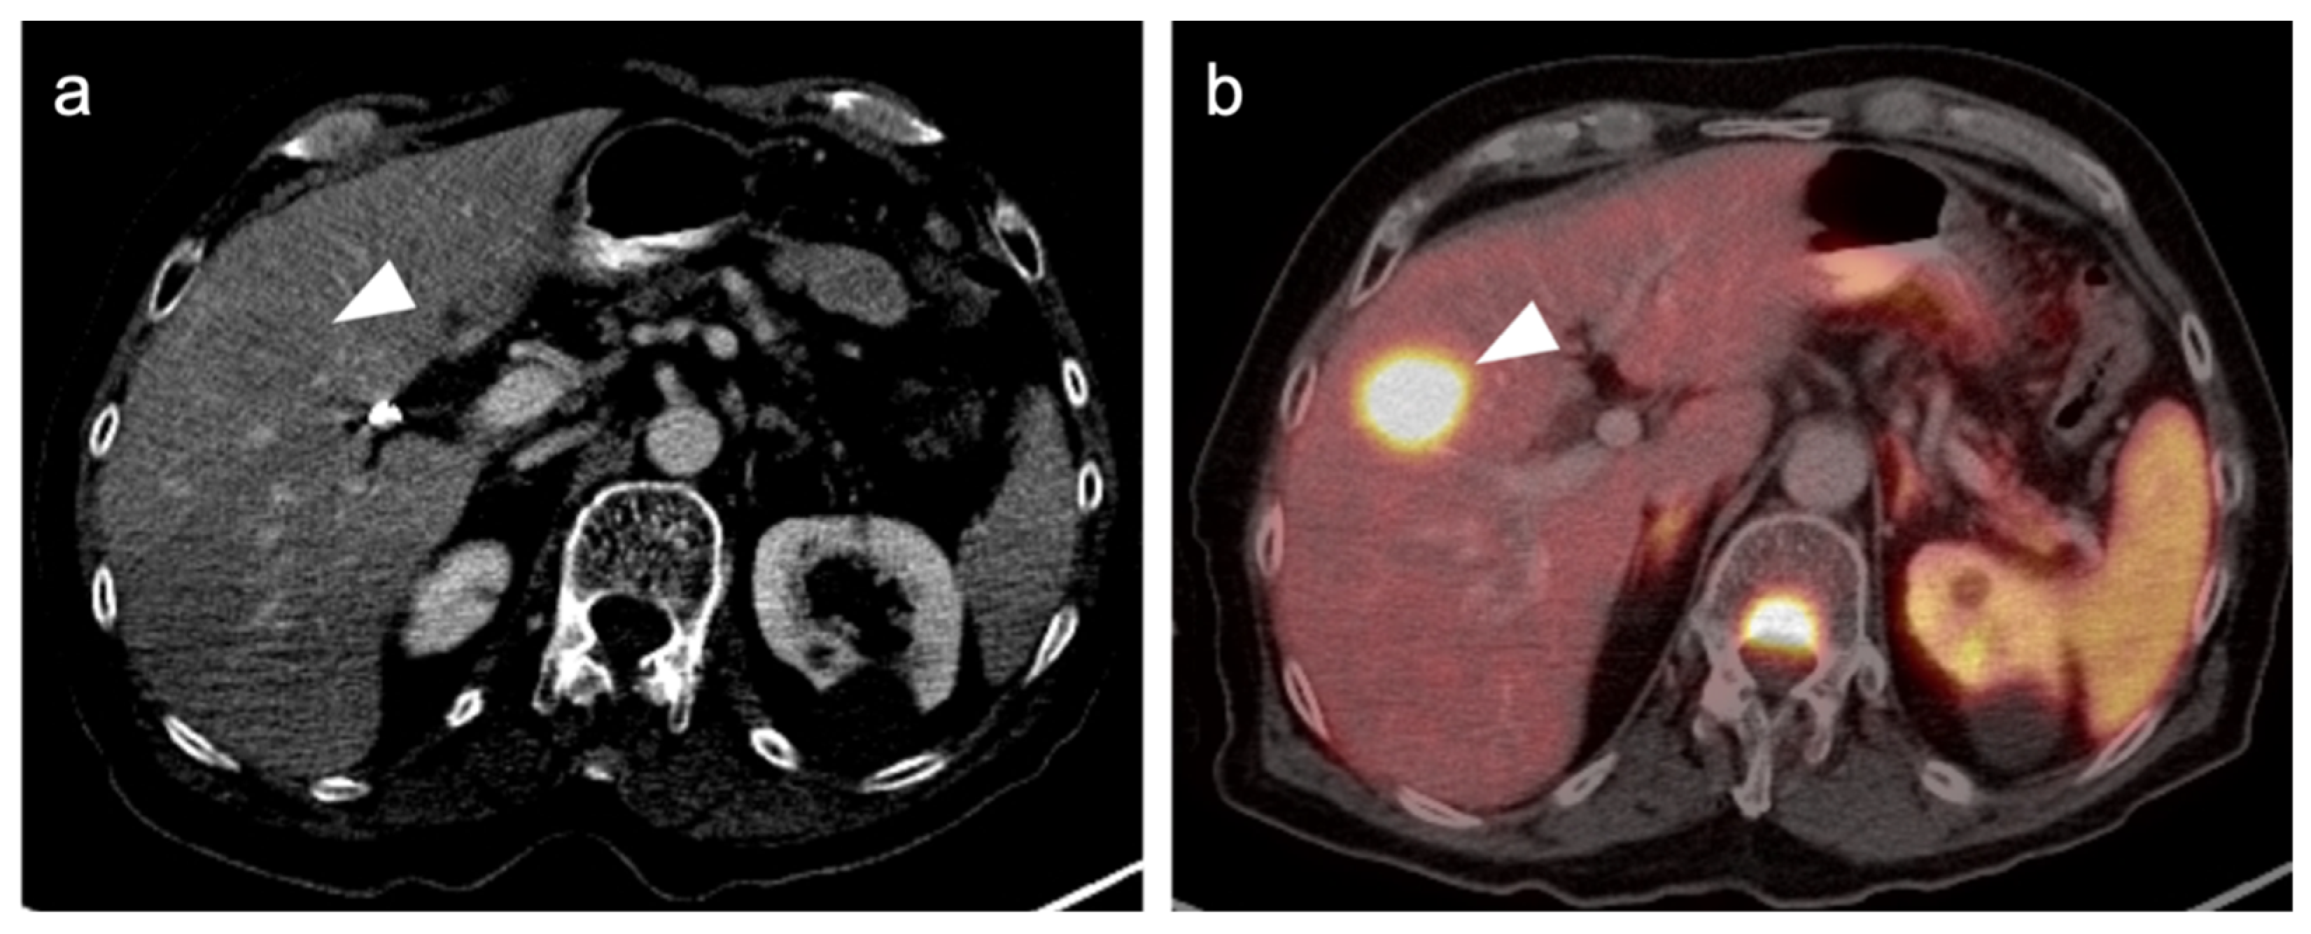

2.3.2. Ocular Melanoma